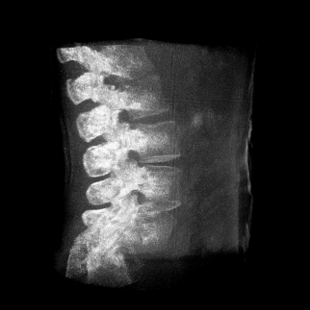

術(shù)中三維成像和橫斷面圖像提供多角度的手術(shù)診斷信息,輔助醫(yī)生進行術(shù)中評估判斷,諸如骨折復位情況和內(nèi)植入螺釘?shù)某叽绾臀恢茫o助手術(shù)更好地完成。

提供更大的術(shù)中三維成像視野,采集更多圖像信息,可一次拍全全段頸椎、全段腰椎、七節(jié)胸椎、雙側(cè)骶髂關(guān)節(jié)、股骨頭及單側(cè)盆骨。

在C臂掃描過程中,始終保持拍攝主體處于射線束的中心,避免了序列圖像采集過程中的橫縱方向運動,減少相對運動造成的運動偽影。